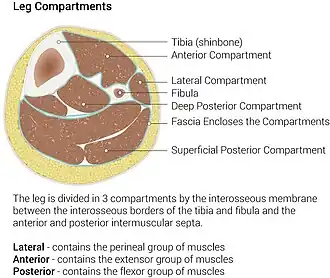

Diagram of leg compartments | |

The posterior compartment of the leg is one of the fascial compartments of the leg and is divided further into deep and superficial compartments.